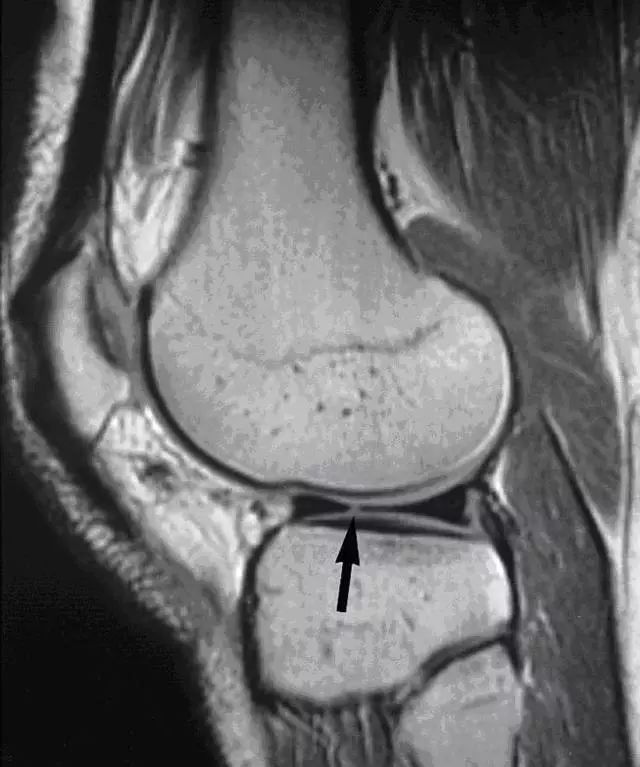

正常半月板 MRI

正常半月板在 MRI 上显示的是低信号,呈「领结形」。外侧半月板呈 O 形,且横断面前后较一致;而内侧半月板较大,曲率较低,后角相较于前角较宽和厚。

内侧半月板外缘完全附着在关节囊上,外侧半月板前角和体部附着在关节囊上,而后角大部分附着在关节囊上,中间由腘肌半月板上下纤维束连接半月板和关节囊,上下纤维束中间形成一裂孔,裂孔中有腘肌腱穿过。示意图如下图 1 所示,正常内外侧半月板 MRI 如图 2 所示。

图 1 可看到外侧半月板后角由腘肌半月板纤维束形成裂孔,其中通过腘肌腱。

图 2 正常半月板